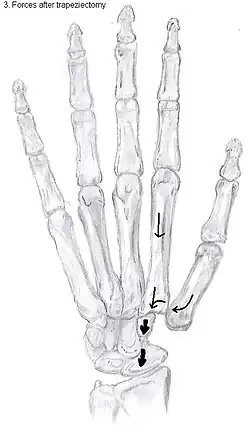

Trapeziectomy

During trapeziectomy,[30] the trapezium bone is removed without any further surgical adjustments. The trapezium bone is removed through an approximately three centimeter long incision along the lateral side of the thumb. To preserve surrounding structures, the trapezium bone is removed "by splitting" it into pieces.

An empty gap is left by the trapeziectomy and the wound is closed with sutures. Despite this gap, no significant changes in function of the thumb are reported.[27] After the surgery, the thumb will be immobilized with a cast.

Trapeziectomy with ligament reconstruction

Another technique is used to reconstruct the volar beak ligament after trapeziectomy. The rationale is that ligament reconstruction(LR) helps maintain the gap between the metacarpal and the scaphoid, and that a larger gap is associated with greater comfort and capability.[32] Again these possibilities are not supported by experimental evidence.

Trapeziectomy with LRTI

Some physicians believe that combining LR with TI will help maintain gap between the metacarpal and the scaphoid.[33] And that doing so will improve comfort and capability. Keep in mind that these aspects of the rationale are not supported by experimental evidence. The evidence suggests that all of these procedures have comparable long-term results.